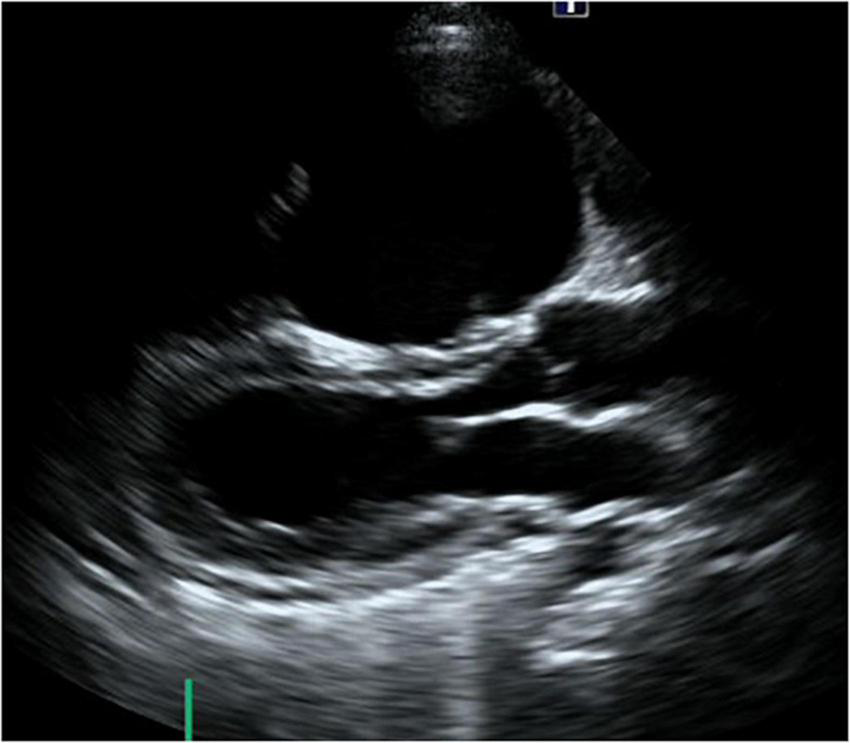

FIGURE 1

Short-axis view at end-diastolic phase of transthoracic echocardiography in Case 1. Note that the right ventricle is much larger than the left ventricle.